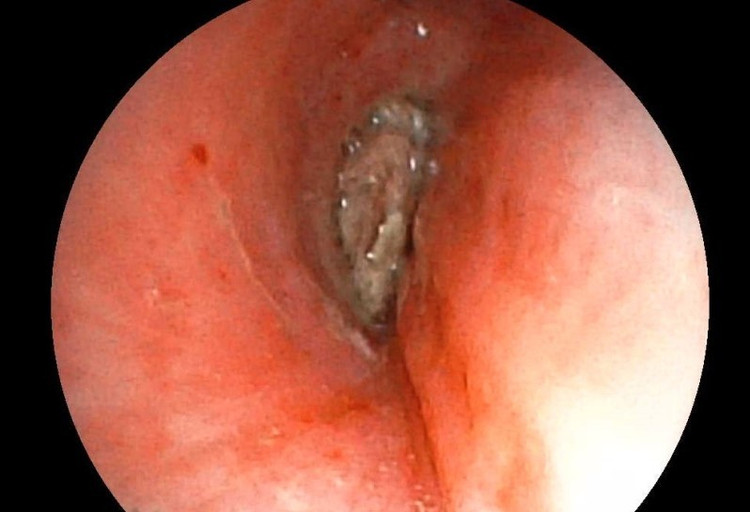

Ê-kíp của bác sĩ CKI Phạm Thị Út Trang – Phó Trưởng Khoa Nội hô hấp đã phối hợp với bác sĩ gây mê hồi sức đã nhanh chóng tiến hành nội soi phế quản ống mềm, phát hiện dị vật góc cạnh khoảng 1cm là hạt kha tử hình bầu dục, bề mặt trơn nhẵn, hai đầu nhọn nằm chắn, gây bít tắc trong lòng phế quản gốc phải, ngay sát vị trí chia nhánh phế quản phân thùy - khu vực giải phẫu hẹp, góc rẽ nhánh phức tạp khiến việc gắp dị vật gặp khó khăn. Ê-kíp nội soi can thiệp đã khéo léo tiếp cận và thành công gắp dị vật ra khỏi lòng phế quản bệnh nhân. Sau can thiệp, sức khỏe của bệnh nhân ổn định, thở dễ dàng, không còn cảm giác tức ngực, được xuất viện sau 24h theo dõi.

Hình ảnh dị vật góc cạnh khoảng 1cm là hạt kha tử hình bầu dục, gây bít tắc trong lòng phế quản. Ảnh BV